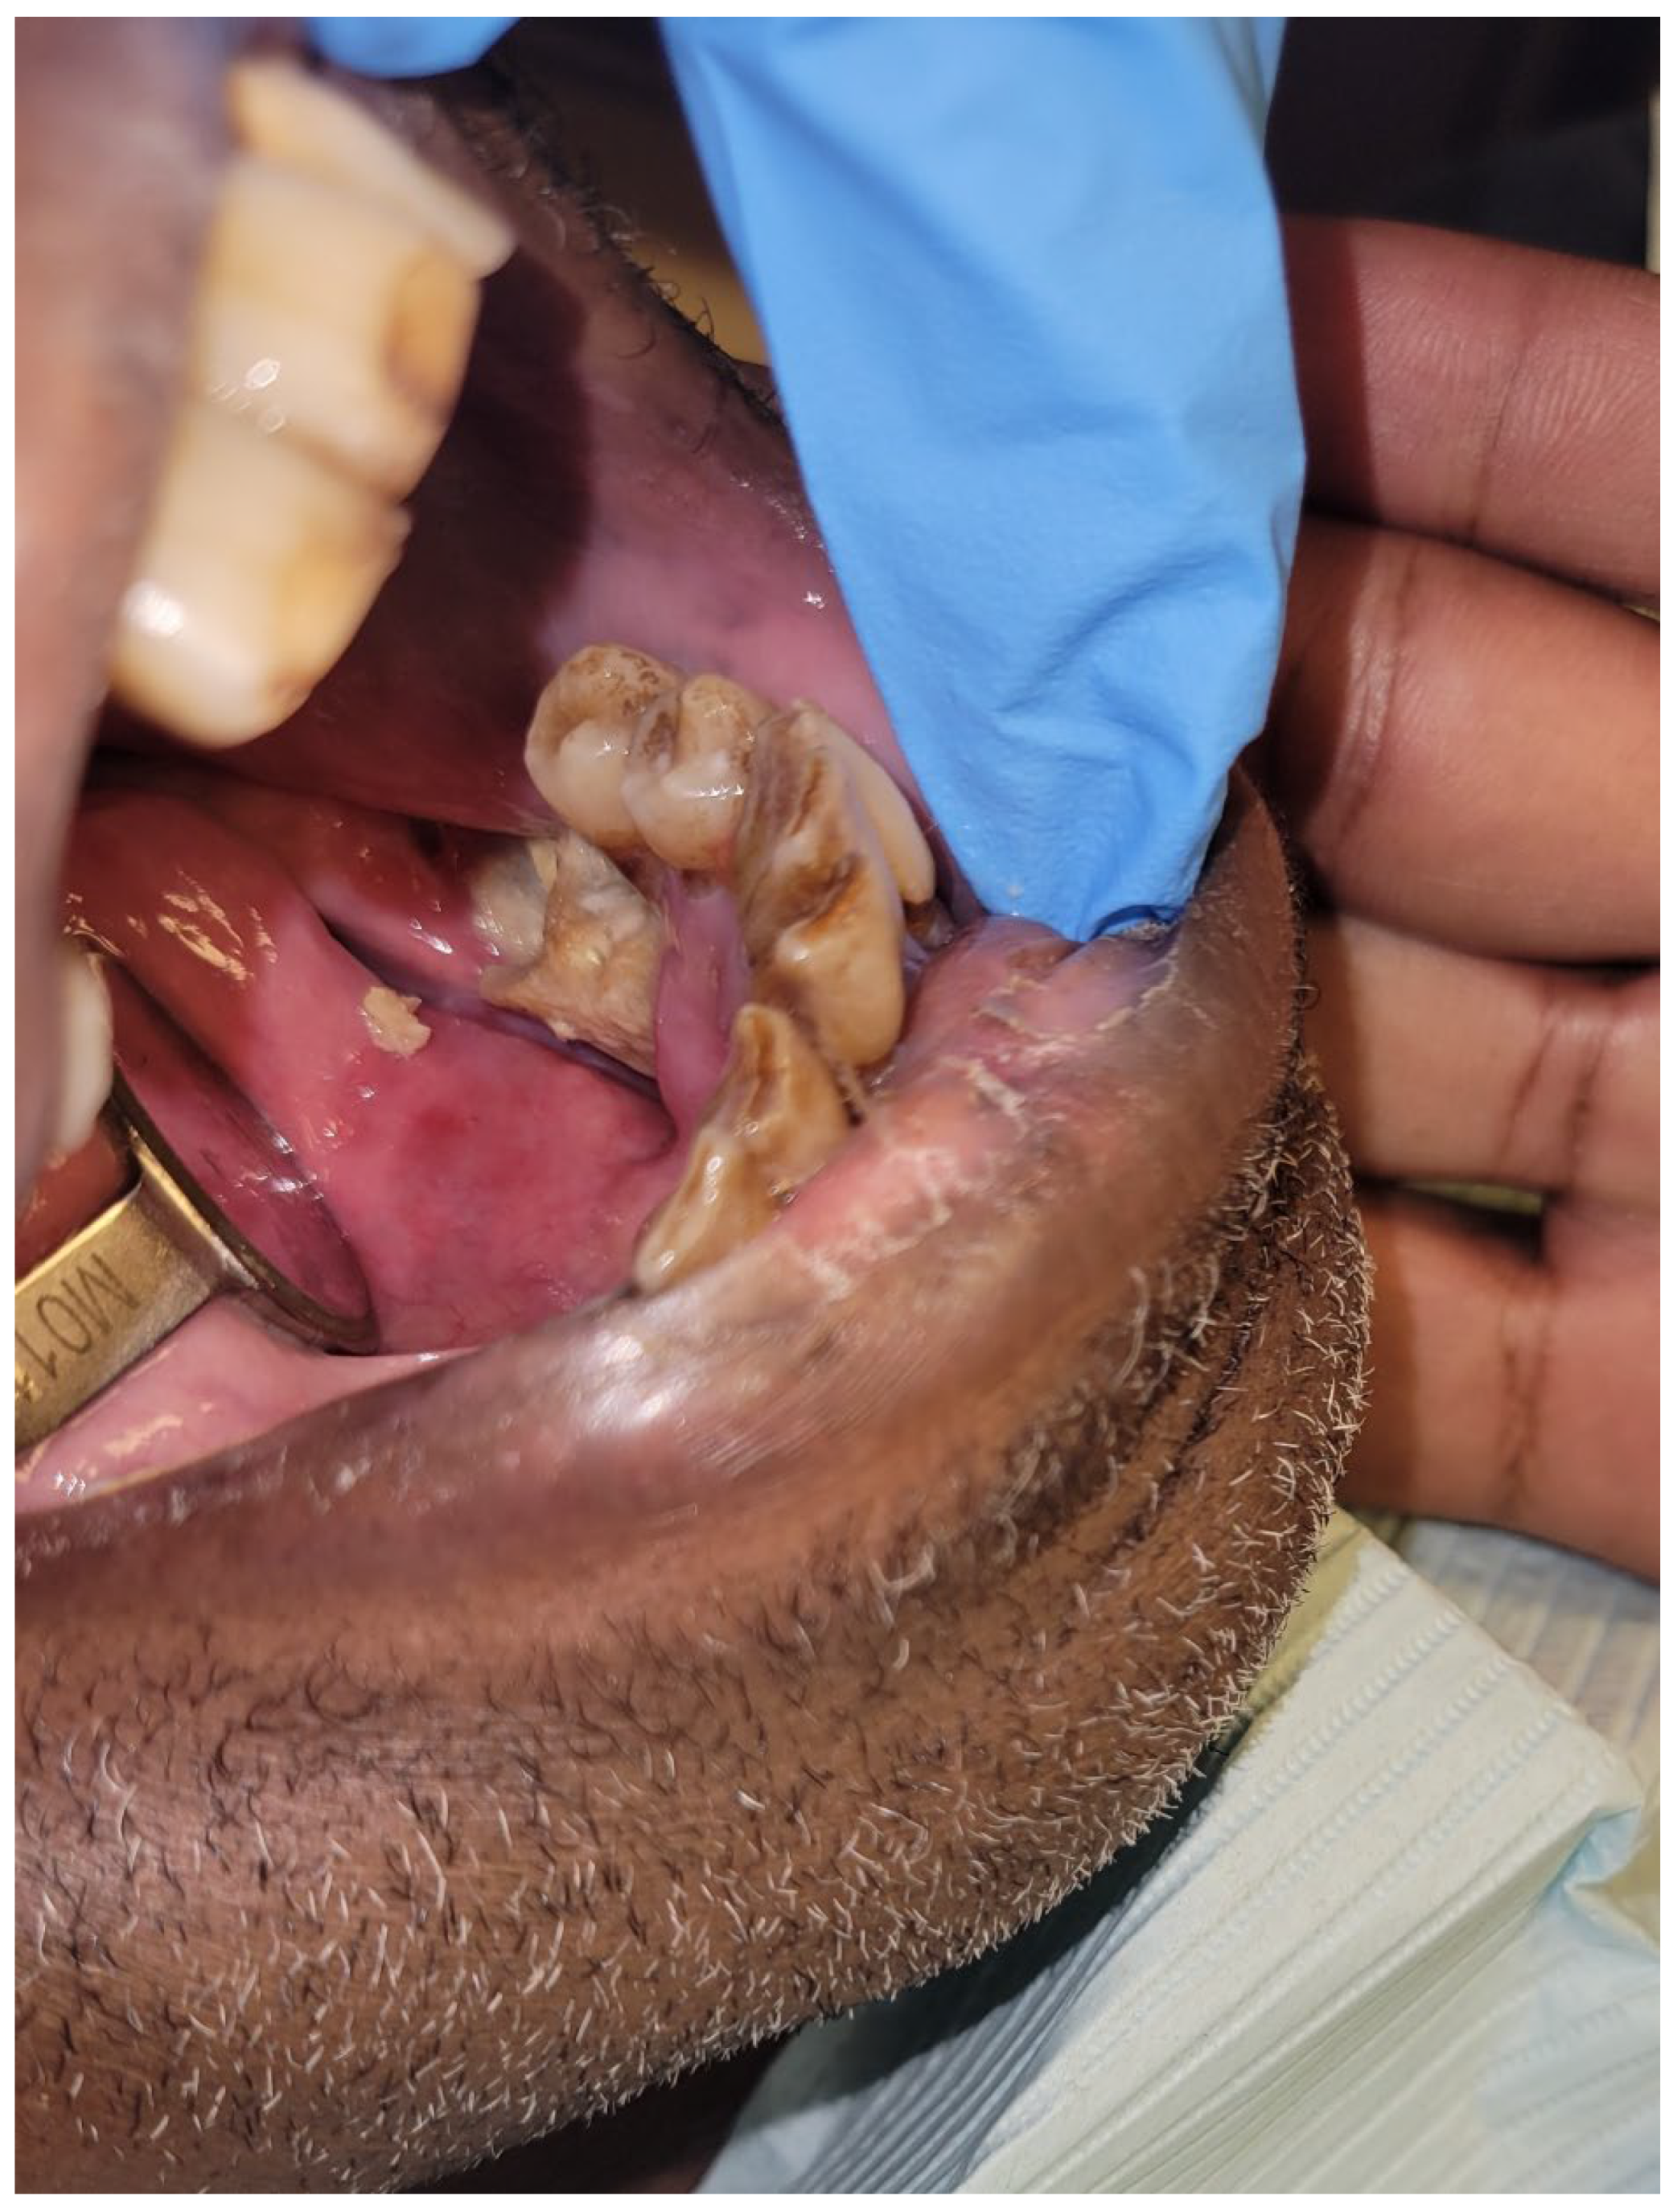

1.4. Osteoradionecrosis

Prevention and Management of Osteoradionecrosis